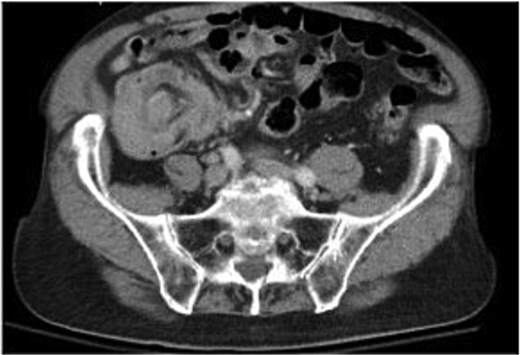

A 79-year-old Spanish-speaking male with hypertension, hyperlipidemia, and benign prostatic hyperplasia presented with intermittent, bilateral lower quadrant abdominal pain and nausea for 3 days. The pain was described as aching, non-radiating, and 6/10 in intensity. He had regular bowel movements and tolerated a normal diet. His past surgical history included a right inguinal hernia repair, and he had a normal colonoscopy 5 years prior, except for benign polyps. Lab work, including a carcinoembryonic antigen (CEA) test (0.5 ng/mL), was normal. A computerized tomography (CT) scan revealed a thickened cecum and ileocecal intussusception (Fig. 1). Gastroenterology performed a colonoscopy with cold forceps biopsies, revealing a large, infiltrative, polypoid mass in the cecum (Fig. 2). Pending pathology, the patient underwent a robotic-assisted right hemicolectomy due to impending bowel obstruction, followed by a functional end-to-end anastomosis. He tolerated the procedure well and was scheduled to begin chemotherapy with Bendamustine and Rituximab, selected due to his advanced age and frailty.

Colorectal MCL presents with nonspecific symptoms like abdominal pain, blood per rectum, fatigue, fevers, and weight loss [6, 7]. In this case, the patient only presented with abdominal pain and nausea. Given these nonspecific symptoms, diagnostic imaging is essential. CT scans help identify masses, lymphadenopathy, tumor size, and invasion depth. In this case, imaging revealed colonic intussusception, leading to surgical consultation. Similarly, Smith et al. [1] reported a case of MCL presenting with intermittent abdominal pain and colonic intussusception. Intussusception due to malignant lymphoma accounts for over 10% of colonic intussusceptions [3]. Colonoscopy and biopsy are key for visualization and diagnosis. In this case, CEA levels were normal, making it an unreliable marker for diagnosis [1, 6].